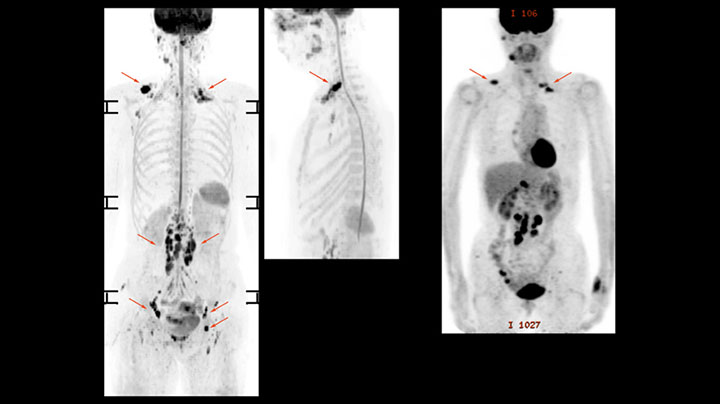

Whole body diffusion

A 61-year-old female with a malignant lymphoma underwent an MRI exam with whole body diffusion weighted imaging (DWIBS) as well as PET. On the images shown, the resolution of DWIBS is better than PET, which allows visualization of the small pelvic lesions and almost no distortion is seen in the neck area.

Whole body diffusion

A 61-year-old female with a malignant lymphoma underwent an MRI exam with whole body diffusion weighted imaging (DWIBS) as well as PET. On the images shown, the resolution of DWIBS is better than PET, which allows visualization of the small pelvic lesions and almost no distortion is seen in the neck area.